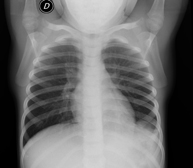

Técnica mediante la cual, utilizando rayos X, se obtienen imágenes de los senos paranasales para su estudio. Indicaciones: cefalea, tos crónica. - RX Tórax

Una radiografía de tórax es una técnica mediante la cual, utilizando una pequeña dosis de radiación, se obtiene una imagen bidimensional de la caja torácica y su contenido (pulmones, corazón, mediastino, etc.). Es una de las pruebas médicas más comúnmente realizadas. - RX Abdomen